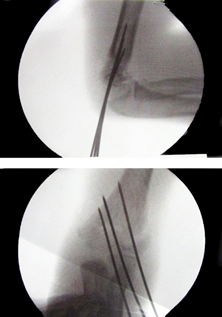

All the fractures united with no loss of carrying angle or cubitus varus deformity. According to Flynn’s grading system for elbow function, 41 patients (89.1%) achieved excellent results and one patient had poor result as shown in Table 2. Five patients (10.8%) had superficial pin site infection that went to heal with local pin site dressings only. None of them had chronic discharge after the wire removal. No complications like ulnar nerve injury, vascular injury, compartment syndrome, myositis ossificans, malunion, and non-unions were noted (Figures 1-4).

Figure 2 Intraoperative fluoroscopic views AP and lateral views.